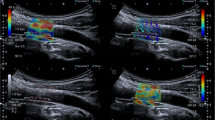

Shear wave elastography (SWE) is a quantitative imaging tool that provides a color SWE map over a greyscale B-mode image. SWE has been used in a wide range of non-vascular applications and found to provide reliable and clinically valuable estimates of tissue stiffness. There are three potential sources of variability: fundamental technical limitations associated with measurement accuracy and repeatability, imaging-related variability, and patient-related confounders [1]. Several previous studies have demonstrated that region of interest size, unit, probe load, anatomical area, breathing, pulsation, and depth can all contribute to variability in SWE measurements [2,3,4]. Acoustic nonlinearity within a tissue can also be a confounder [5]. Although these sources of variability have been reported, the relative contributions of confounders have not been fully investigated. Understanding and identifying sources of variability in SWE measurements will be essential in determining whether the SWE technique is sufficiently sensitive to small differences in YM associated with pathology. Additionally, acquisition standardization may help reduce manufacturer variability which may improve our ability to evaluate scanner performance.

SuperSonic Imagine Aixplorer ultrasound imaging system was used to assess the variability of SWE measurements at different CCA locations in Young’s modulus (kilopascal, kPa) using a curvilinear 4–15 MHz transducer. Measurement was obtained by an experienced certified clinical sonographer with efficient training on ultrasound SWE.

SWE image analysis

The SWE scans were analyzed retrospectively, and arterial wall YM was quantified using the Aixplorer’s in-built analysis software for 2 mm ROIs. ROIs were placed in different CCA locations to assess the variability of YM measurements with ROI position as shown in Fig. 5. The locations include anterior, posterior, left, right, distal, and proximal. Criteria for inclusion of measurements in further statistical analysis were as follows: (1) good image acquisition; (2) complete filling of the shear wave elastogram; and (3) adequate cine-loops. Exclusion criteria included are as follows: (1) poor image acquisition; (2) insufficient shear wave elastogram filling; and (3) cine-loops with less than five SWE frames.

SWE technology has been used in many applications, but its suitability for vascular applications remains hotly debated. It has been proposed that SWE might have potential clinical value in the diagnosis of vascular disease, and in particular, detection of early changes in arterial vessel elasticity [19]. However, concerns have arisen over the reliability of SWE YM estimates and the potential impact of factors such as ROI size and position on YM estimates. Ultimately, if measurement variability is greater than typical clinically significant differences, this will limit the usefulness of SWE in clinical practice. This study focused on the identification and quantification of sources of variability in arterial wall SWE measurements (Fig. 5).